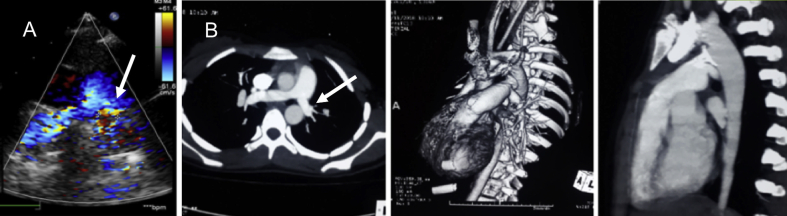

Fig. 4.

Follow-up transthoracic echocardiogram shows mild turbulence in the left pulmonary artery (peak gradient 15 mm Hg) (A, arrow). A computed tomography angiogram showed the device-in-situ, normal sized right PA (12 mm) and diffusely narrow left PA (8 mm) (B, arrow).

There was no death or device embolization in the study cohort. In one patient, there was 90% obstruction of the aorta before the release of a 30/28 mm Cera occluder, which was tackled by removing the unreleased device and deploying a smaller 24 mm Cera MVSDO, as previously described (Fig. 3).6 One patient developed hemolysis due to residual flow after the deployment of a 24 mm ASO and needed surgical intervention. One patient had partial obstruction of the left PA (gradient 30 mm Hg on echocardiography), which was managed conservatively in view of the absence of symptoms (Table 1). A repeat echocardiogram at 1-year follow-up showed reduction in gradient (15 mm Hg) (Fig. 4). At the end of the procedure, angiographic trivial or mild residual flow across the device was seen in 10 patients.